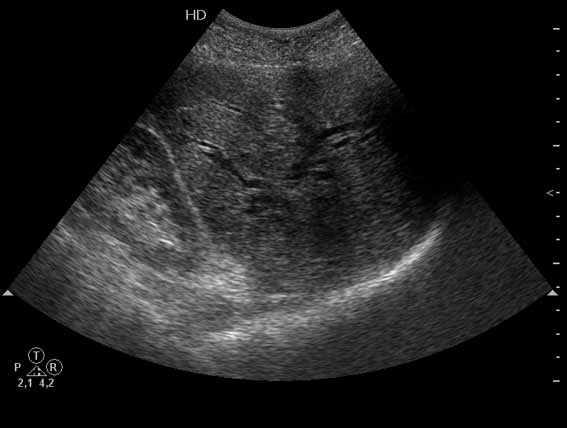

Не могу сказать что я вижу камень в холедохе на представленных сонограммах. Холедох расширен; интра-печёночные жёлчные пути тоже (значит прошло > 3 недель от момента обструкции). Жалоб на сильные приступообразные боли я не прочёл. Всё таки буду думать сначала о опухоли (если при УЗИ не нашли камня); рекомендация-таргетное КТ печени и поджелудочной.

Гнойный холангит на фоне обструкции БДС конкрементом (камень вне скана). В холедохе определяется желчь с осадком, которая может быть ошибочно принята за его опухоль.